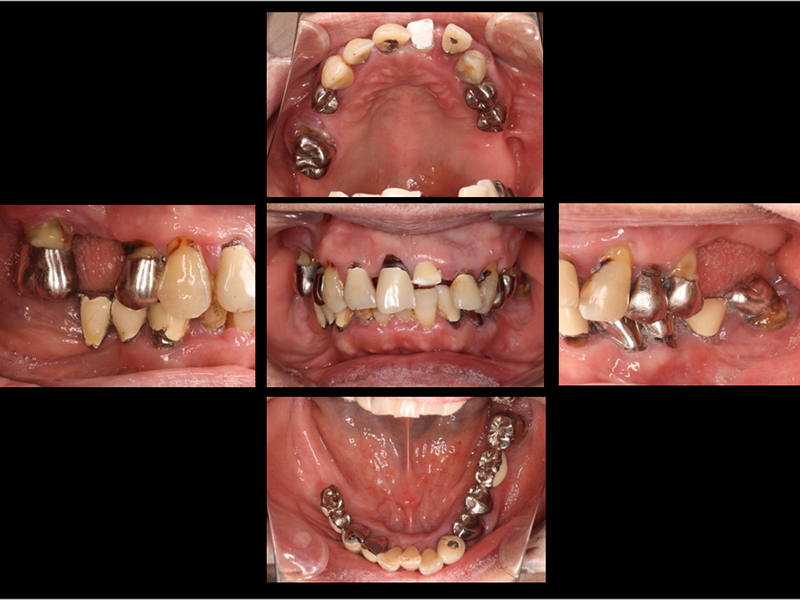

治療前の口腔内写真